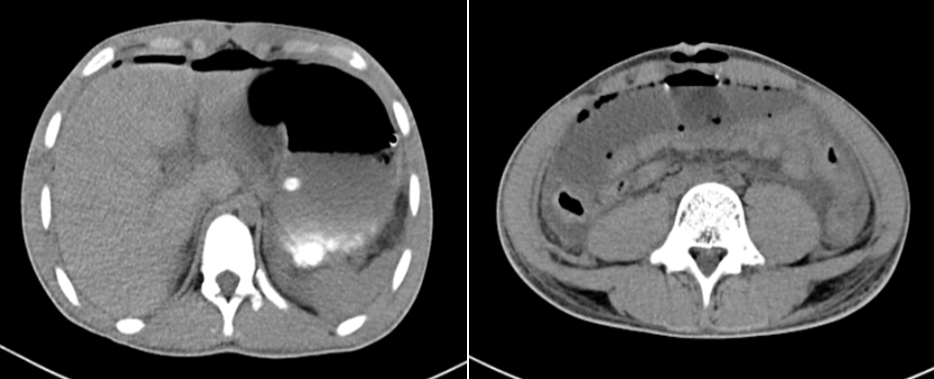

Bệnh nhân nam, 15 tuổi vào viện vì tai nạn giao thông ngày 01/01/2023. Ghi nhận lúc vào viện tại khoa cấp cứu lúc 15h20: Bệnh nhân tỉnh, tiếp xúc chậm, Tim nhịp đều nhanh 125l/p, mạch quay bắt yếu, HA 60/40, Bụng hơi chướng, xây xát bụng vùng dưới rốn. Chụp cắt lớp vi tính toàn thân: Dịch ổ phúc mạc lượng ít, Không hơi tự do ổ phúc mạc, không vỡ tạng đặc. Gãy ngành chậu mu và ngồi mu (P) Gãy giữa xương đùi (P). Được chẩn đoán: choáng đa chấn thương và chuyển khoa hồi sức tích cực

Hình ảnh chụp cắt lớp vi tính ổ bụng lúc mới vào viện